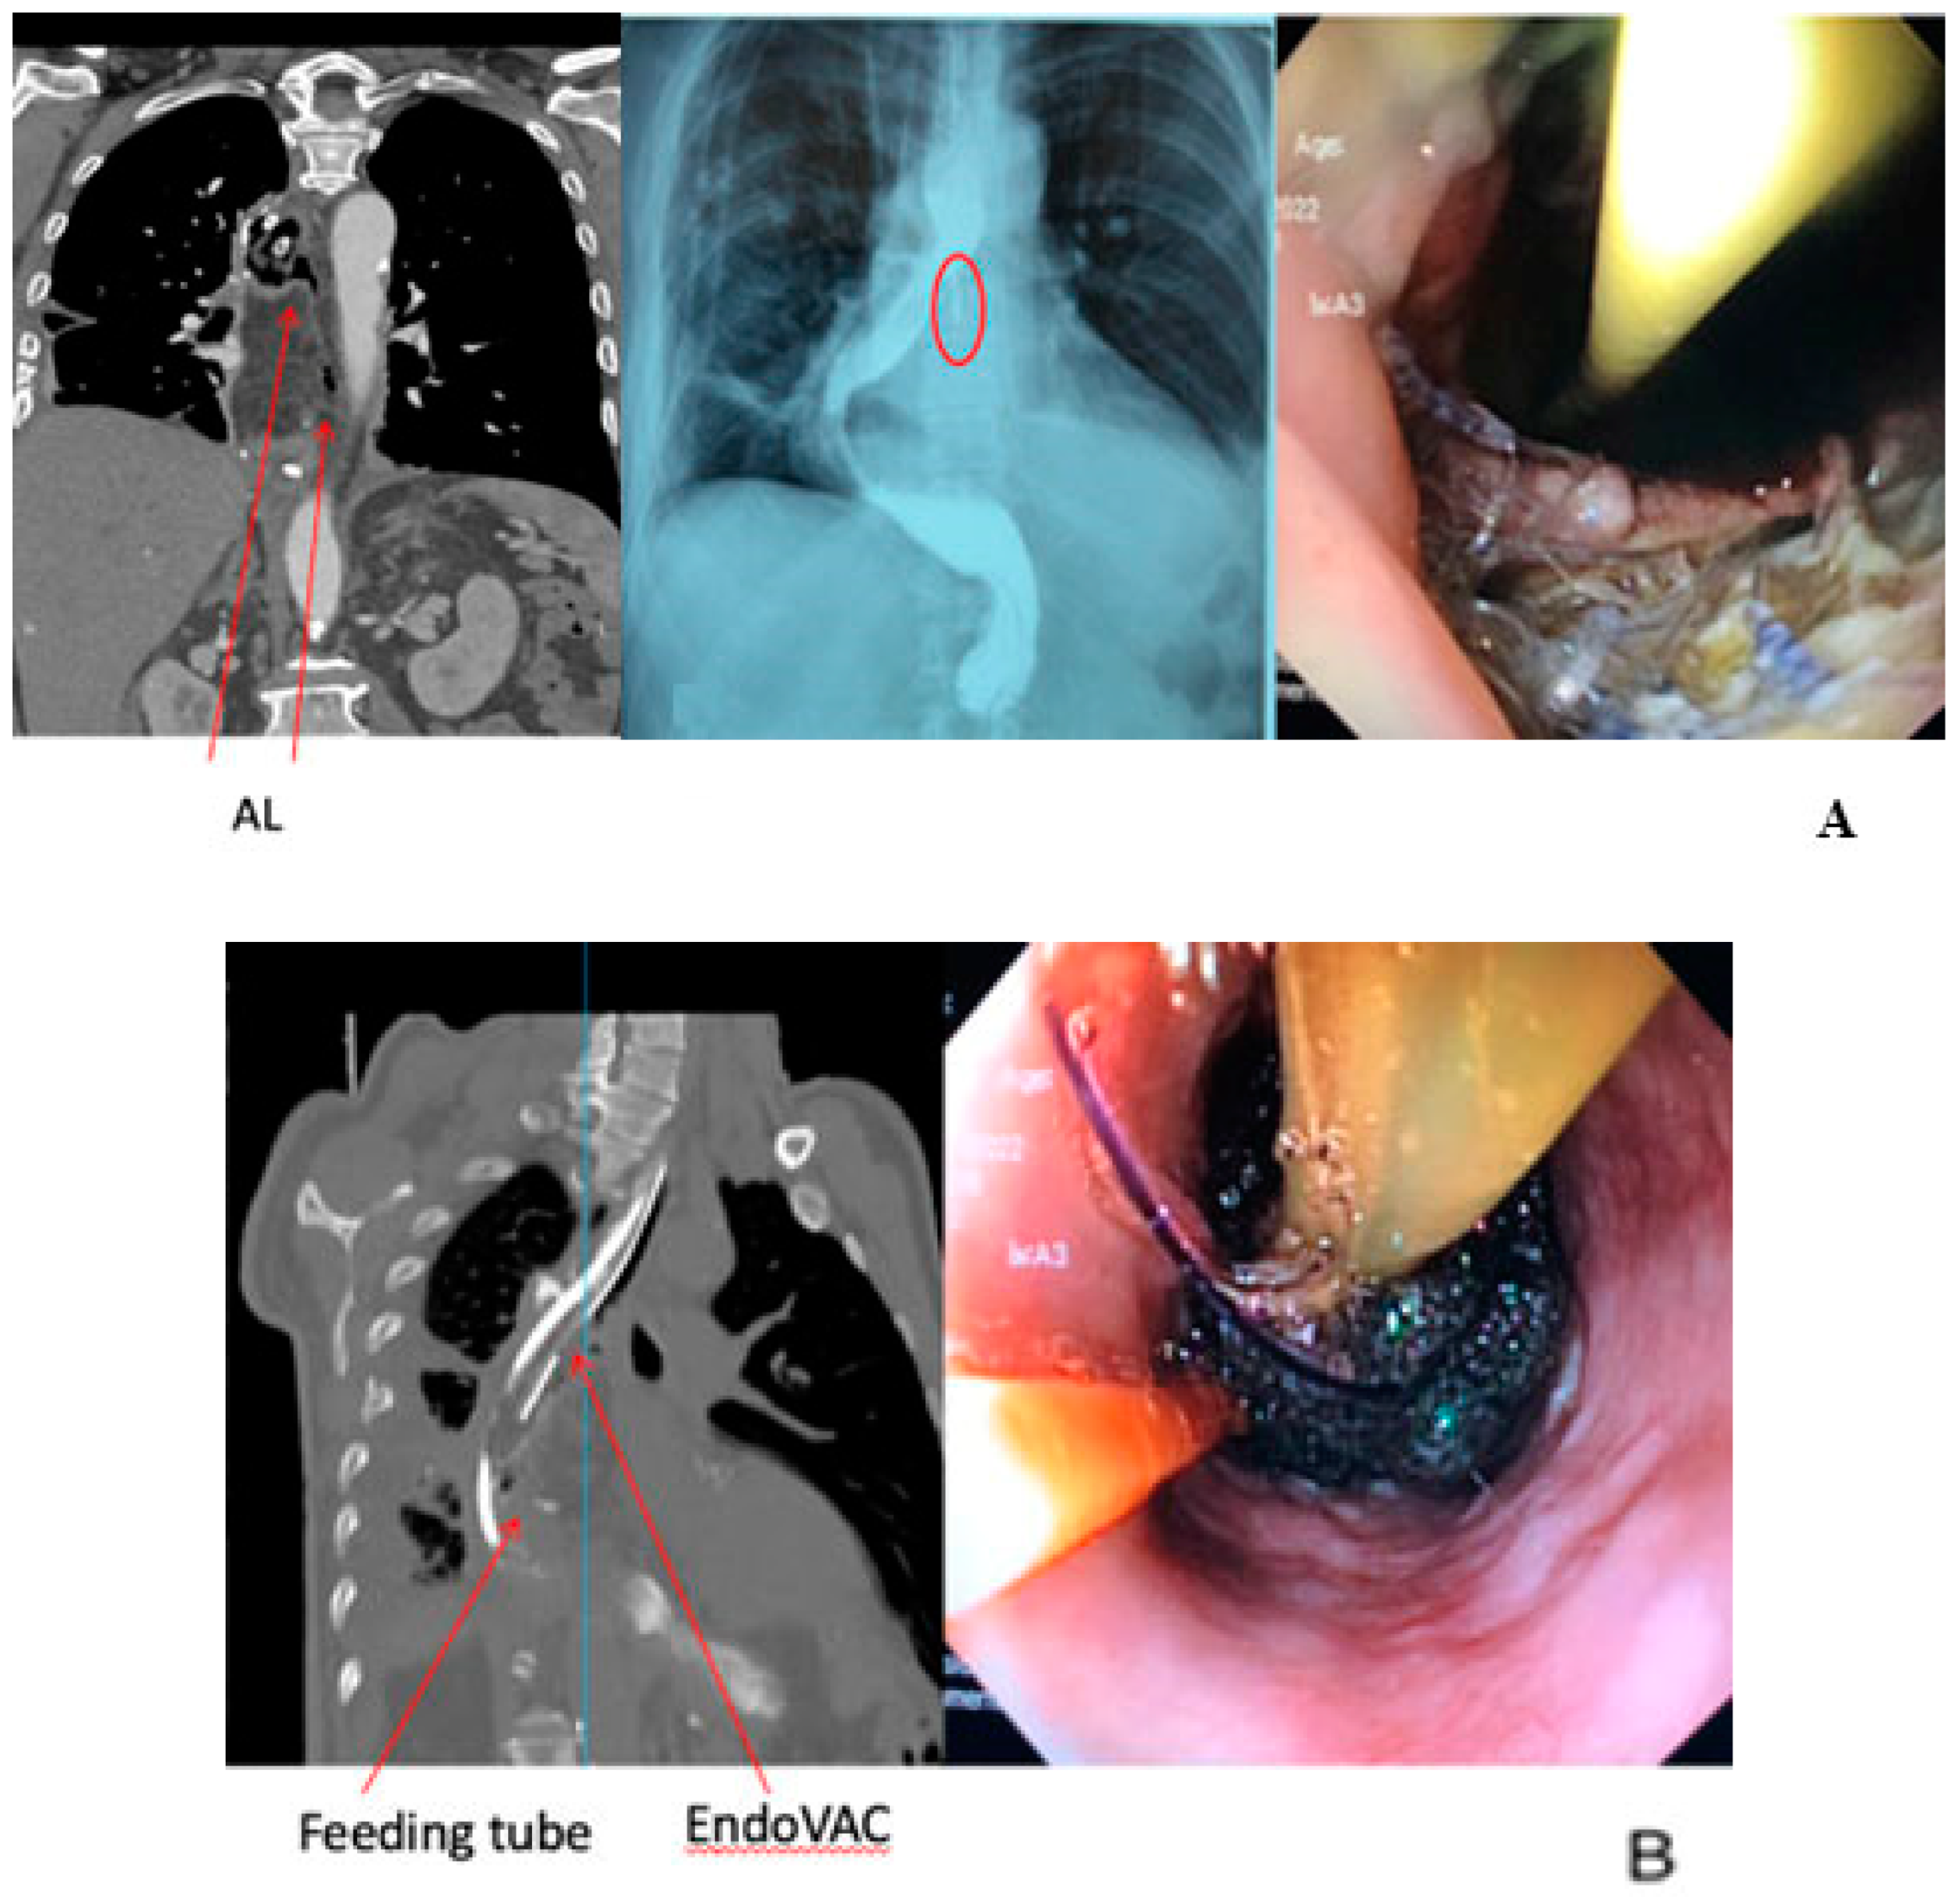

3. The Role of EndoVAC in the Management of EC Anastomotic Leakage